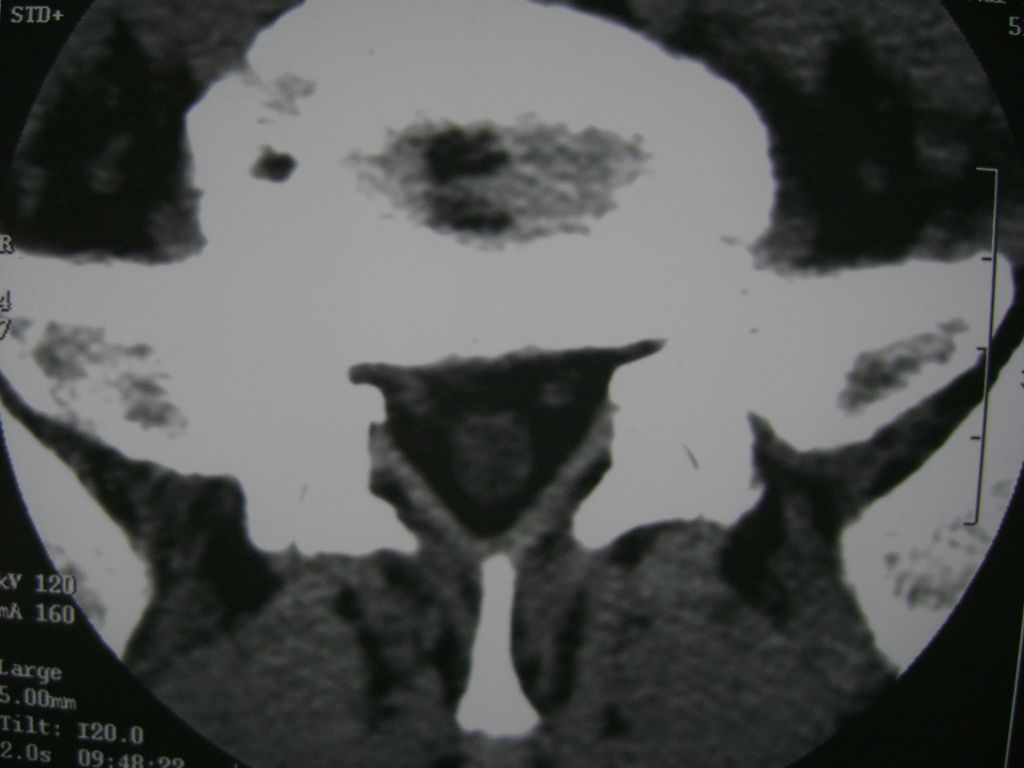

m  50  腰痛

两个椎盘均有膨出及突出改变,下一个尚有椎盘积气,后纵韧带钙化,另椎管脂肪过多症

椎间盘膨出,后纵韧带钙化,骨质增生

两个椎间盘中央型重度突出,黄韧带增厚。

两个椎间盘膨出并突出,下一个椎间盘变性;双侧黄韧带钙化。